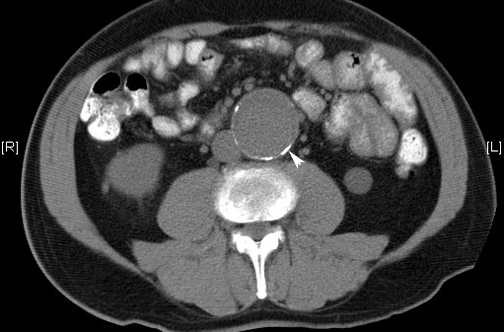

Cuestionan la eficacia actual del rastreo de aneurisma aórtico

Hay un descenso de la incidencia de mortalidad en las últimas décadas que excede a los efectos del rastreo, y que vuelve menos claro el balance de los riesgos y los beneficios del cribado. The Lancet, 14 de junio de 2018